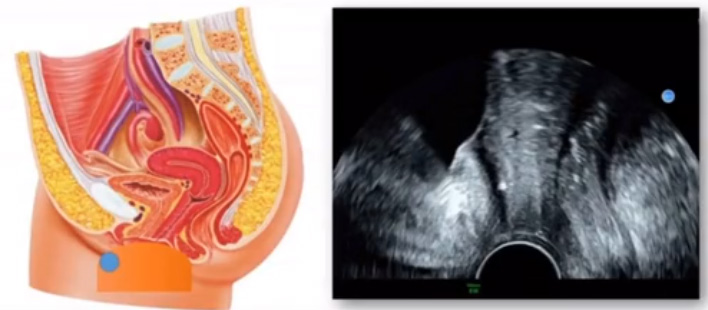

位于輸卵管的后下方,子宮兩側(cè)的后上方;借卵巢系膜與子宮闊韌帶后層相連。正常成人卵巢約4x3x2cm,跟睪丸的數(shù)值差不多,都是性器官,絕經(jīng)后卵巢萎縮變小、變硬。所以絕經(jīng)后婦女很難找到卵巢,主要功能:生殖和內(nèi)分泌功能分泌性激素。女性的第二性征。女性內(nèi)生殖器的血管分布,動脈有子宮動脈,卵巢動脈,陰道動脈,陰部內(nèi)動脈。靜脈它是與動脈伴行。重要了解的是子宮動脈,子宮動脈是髂內(nèi)動脈前干的重要分支,妊娠時候血流速度會增加的,為無創(chuàng)性檢查胎盤血管阻力的方法。未孕期頻譜為高阻力低舒張波形;正常妊娠時血流速度增加,血流阻力下降。